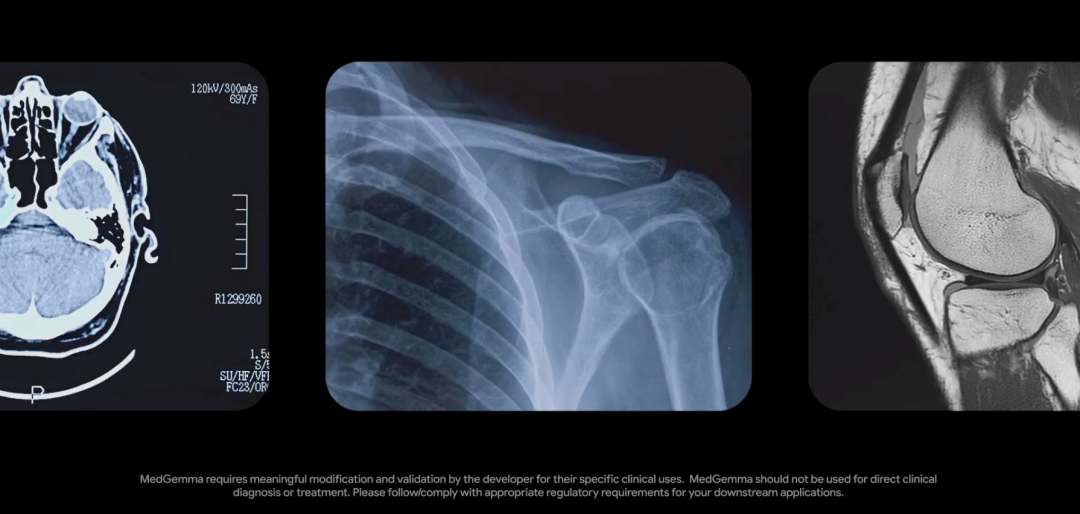

5月,谷歌DeepMind曾开源了强大的医疗模型MedGemma,在多模态医学文本和图像理解上表现优异。

三、多模态深度赋能临床

影像和文本,从来不是两条独立的信息链。

山海·知医大模型5.0升级后,兼具「看懂影像」和「读懂文本」的双重能力。

它不仅能精准识别X光、CT、MRI等影像中病灶,还能将影像特征映射到医学语义空间中。

也就是说,它可以实现影像特征与临床描述的跨模态语义对齐及联合推理。

这就好比为医生配备了「图文协同」智能助手,大幅提升诊断的精准性与效率。